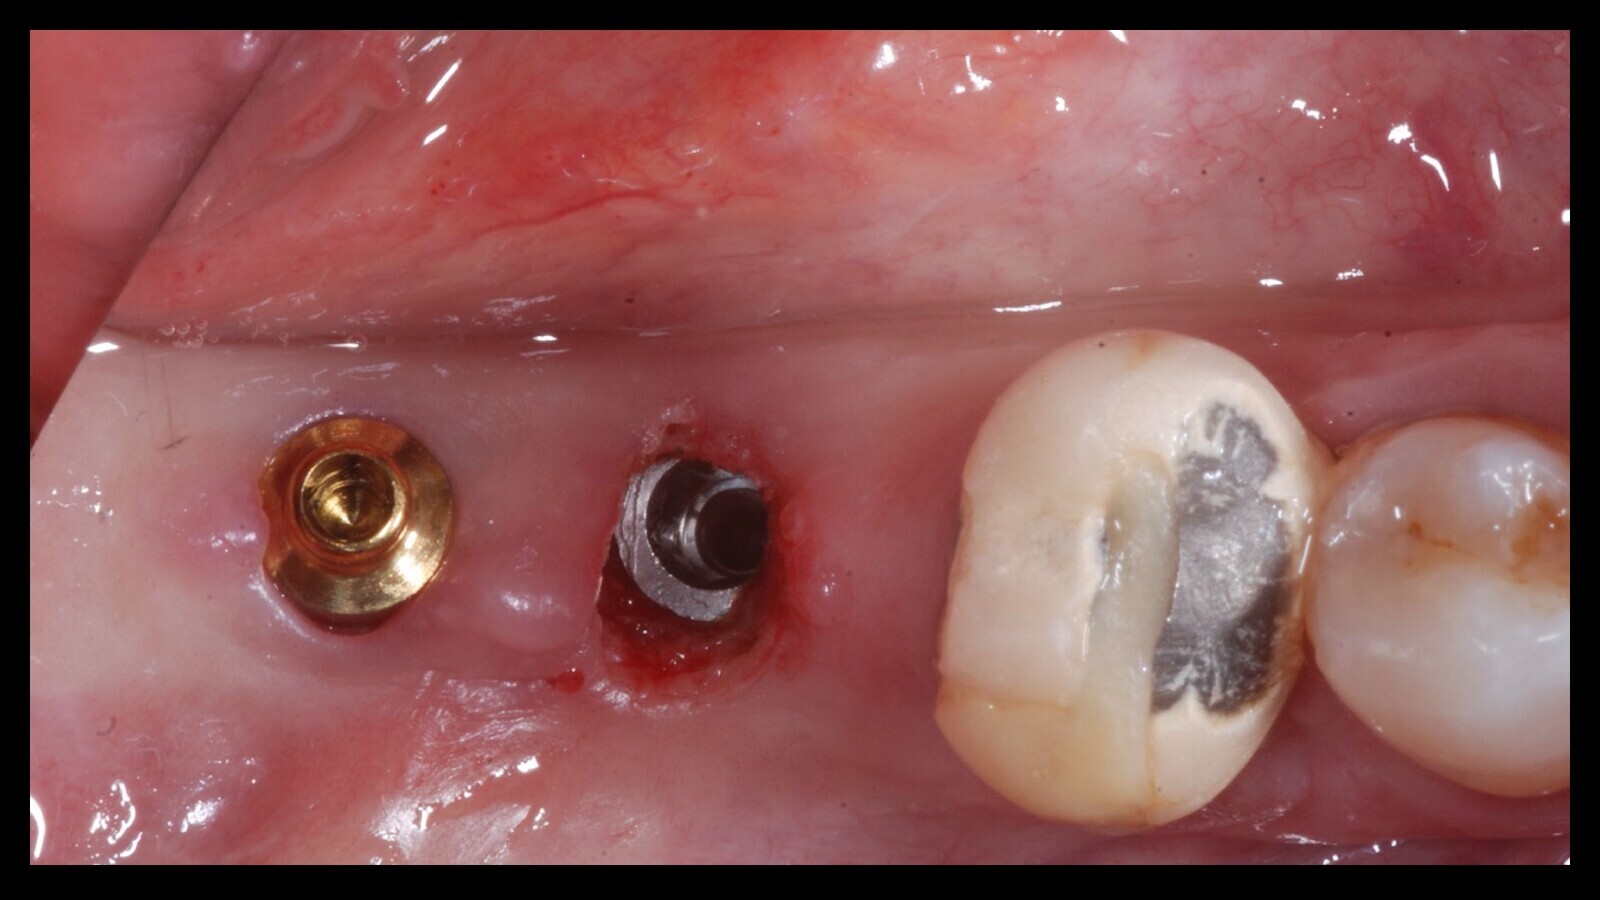

Figura 12. Durante la misma cita, se posicionaron los Equator con la técnica tradicional, como se observa en estas dos imágenes.